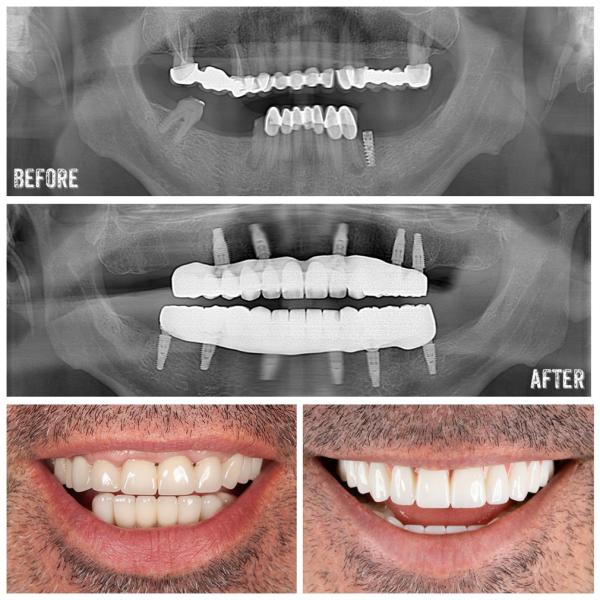

Tandimplantat i Antalya : Implantat i Turkiet är en permanent lösning för saknade tänder och är vanligtvis mer prisvärda samtidigt som de använder avancerade kirurgiska tekniker.

Hela munrestaureringar : Patienter som behöver flera behandlingar drar ofta nytta av heltäckande tandvårdspaket som kombinerar behandlingar.

Moderna kliniker i Antalya är utrustade med avancerad teknik som digital röntgen, 3D-avbildning och CAD/CAM-system , vilket säkerställer precision och effektivitet. Många tandläkare är internationellt utbildade, med stark betoning på hygien och patientsäkerhet. För brittiska patienter som ofta oroar sig för frågan "Är det säkert att få tandvård i Turkiet?" , ligger svaret i det växande globala erkännandet av Antalya som ett pålitligt centrum för tandvårdsturism.